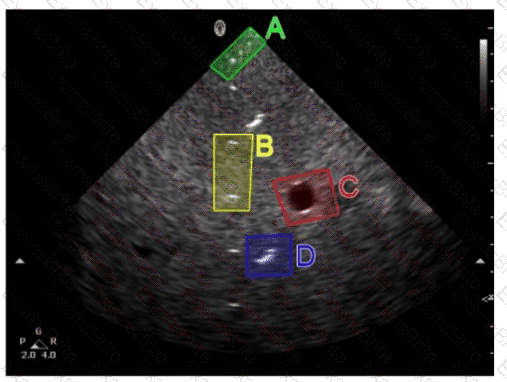

Questions 18

Which target group is used to evaluate transverse distance measurement accuracy in this tissue-mimicking phantom image?

Options:

A.

Option A

B.

Option B

C.

Option C

D.

Option D

Discussion 0